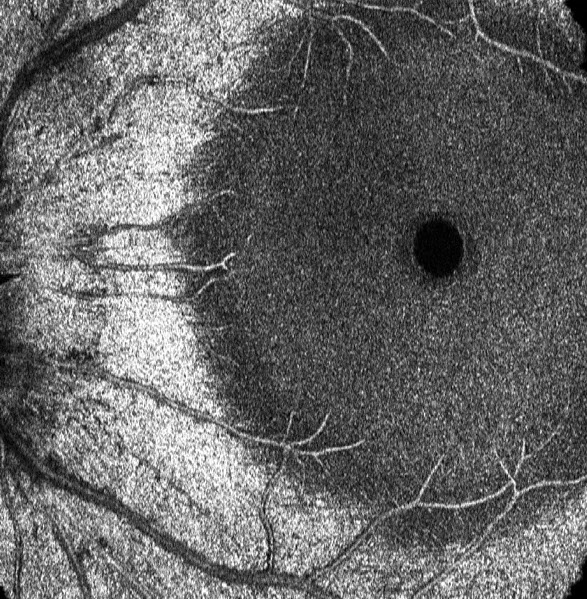

OMAG is capable of providing (a) retinal microvasculature maps within a large field of view, and (b) the corresponding color depth-encoded retinal vasculature map (the red, green and blue represent the GCL, IPL and OPL respectively).

High resolution OMAG retinal vasculature network images reveal clear details of the vessel interconnections, particularly for the capillary blood vessels. (a), (b) and (c) present the blood vessel networks located at the GCL, IPL and OPL layers, respectively. (d) is the false color depth-encoded blood vessel images by combining together the vessels presented in (a), (b) and (c). The red, green and blue are corresponding to GCL, IPL and OPL respectively.